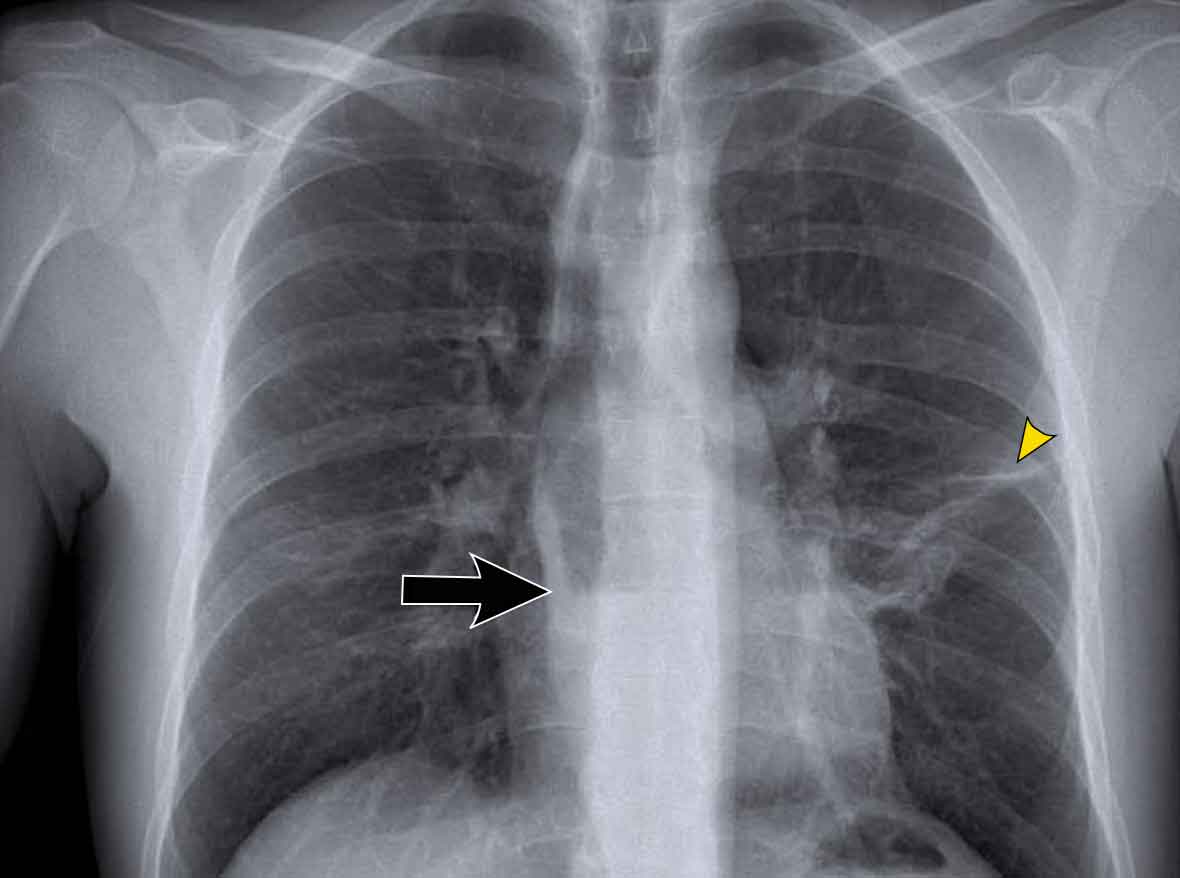

On the chest X-ray, note superior displacement of the azygoesophageal line just below the carina, consistent with enlarged subcarinal lymph nodes (black arrow).

Additional right paratracheal lymphadenopathy is seen, displacing the right paratracheal stripe (white arrow) and deviating the trachea to the left.

Continue with PET-CT...

CT Imaging

• Contrast-enhanced CT shows bulky subcarinal lymphadenopathy displacing the azygoesophageal recess and compressing the left atrium.

• Biopsy of a cervical node confirmed small cell lung carcinoma.